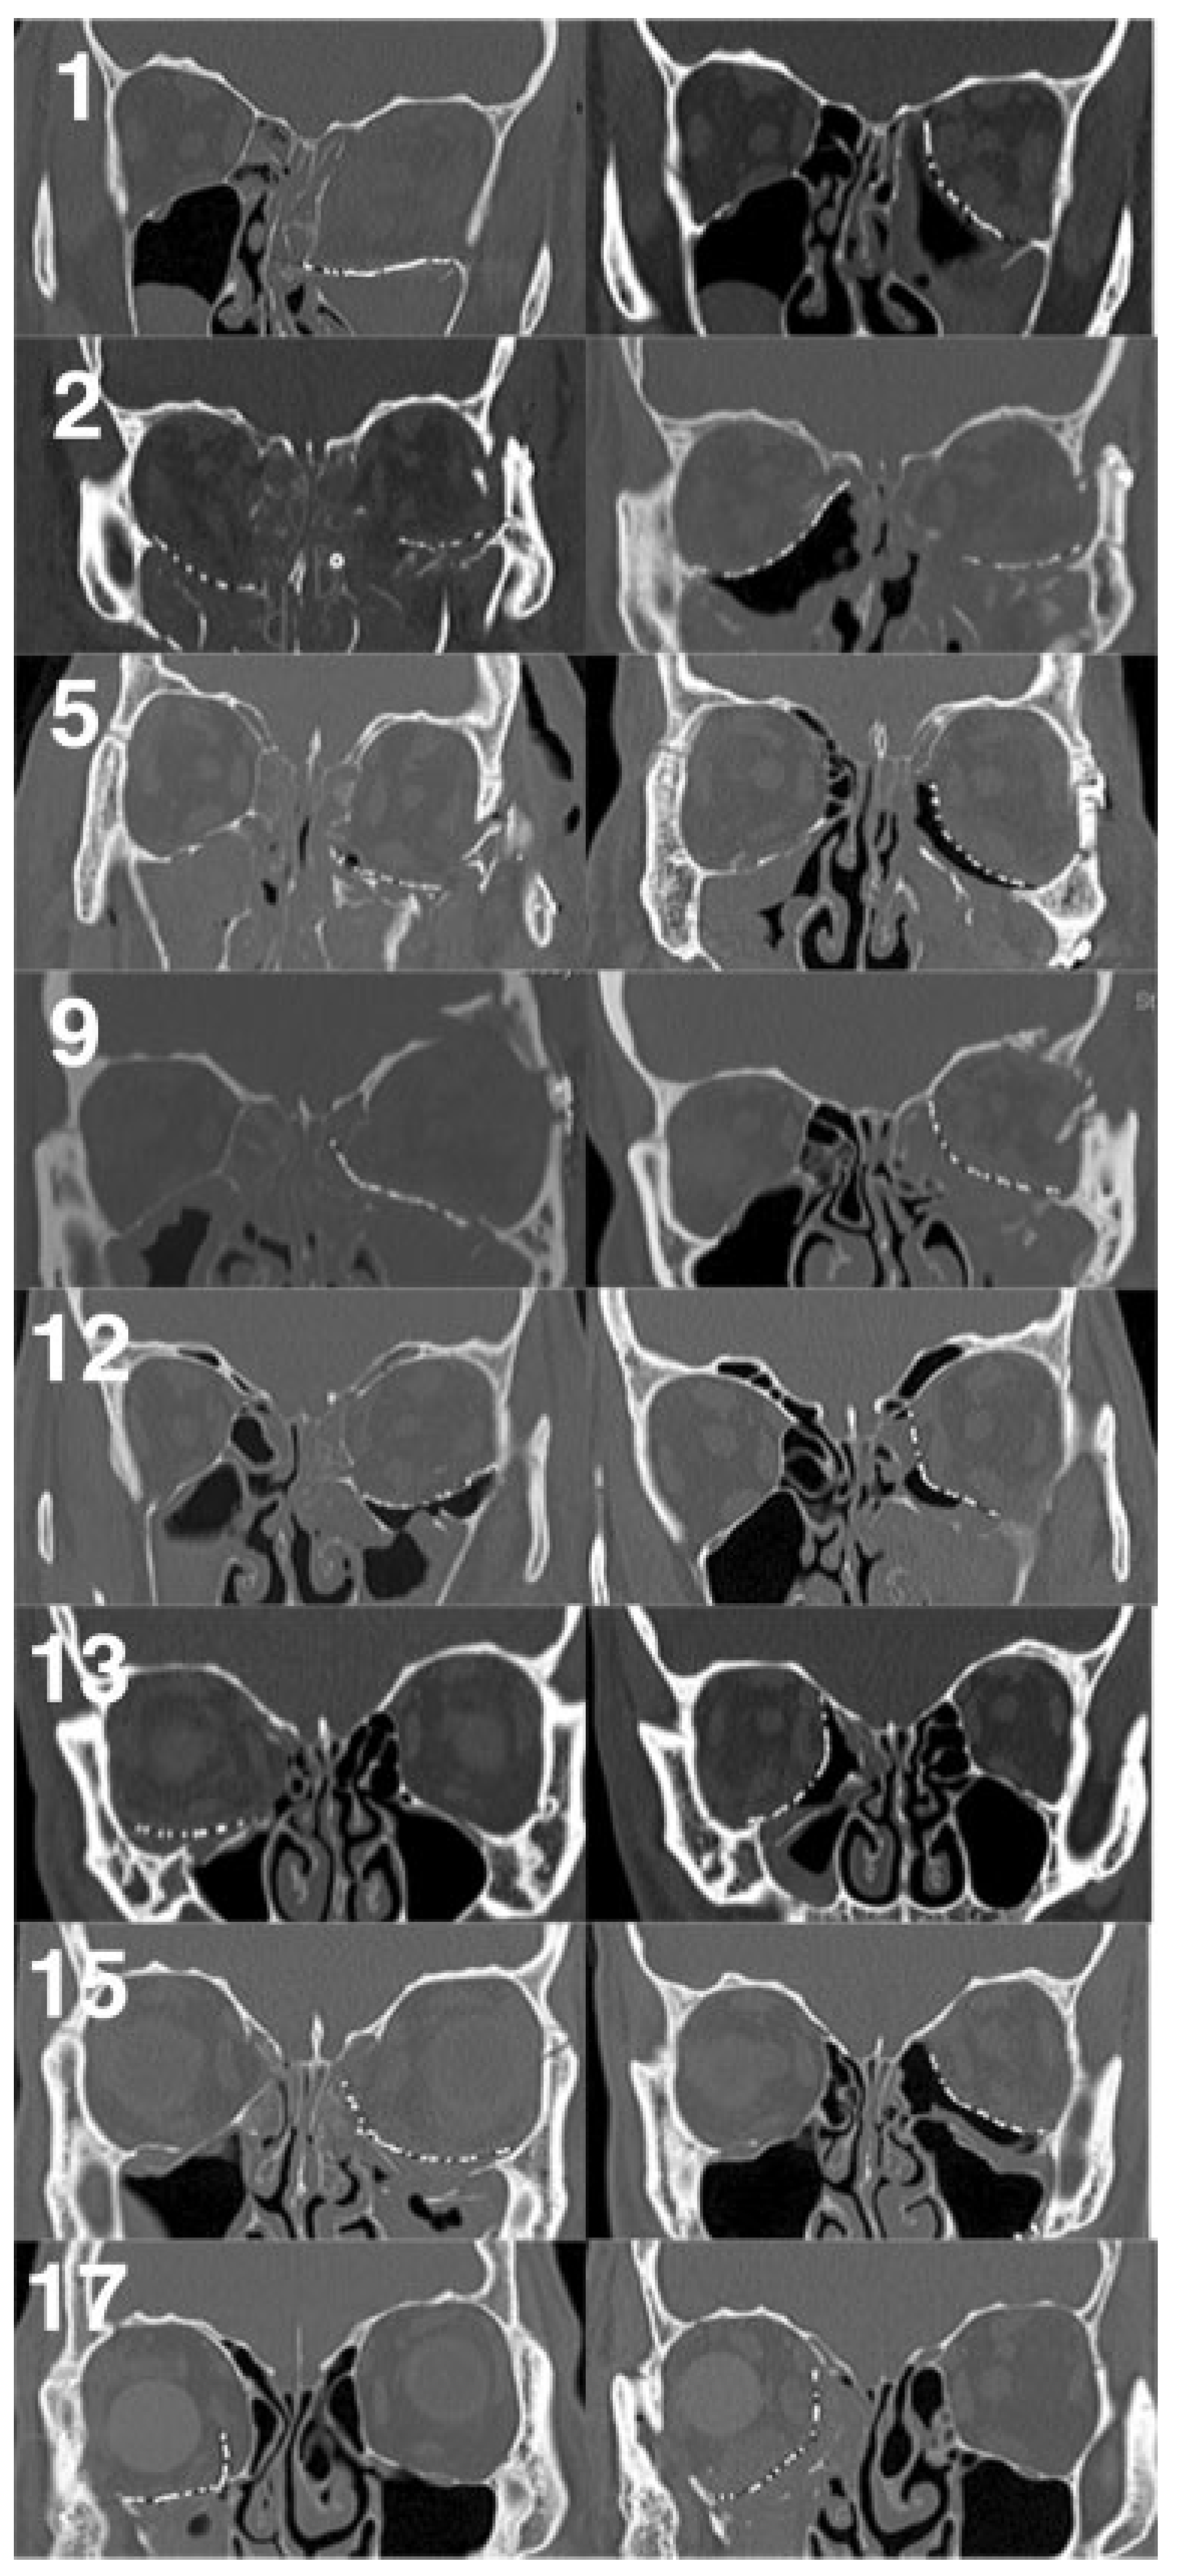

Exophthalmometry measurements were excluded in four patients with acquired anophthalmos of the operative or fellow orbit, and were unavailable in two others. In the remaining 11 cases, the average asymmetry in postoperative Hertel measurements was 1 mm (range 0 to 2 mm). Analysis of preoperative CT scan imaging (Figure 4) revealed preopera-tive orbital volume expansion in all cases, with an average of 122.8% (range 108 to 147%, standard deviation [SD] 9.6). The average postoperative orbital volume was 100.3% of control (range 92 to 110%, SD 5.7), with an average postoperative decrease in orbital volume of 22.5% (range 10 to 54%, SD 11.4, p < 0.001).

Positioning of the implant on stable ledges of bone is also critical, as no implant, no matter how well designed or shaped, will serve its purpose if not placed anatomically. Anterior and lateral bony ledges are relatively easy to obtain, but the most important and most problematic support points are the posterior and superior ledges. Failure to support the implant on these ledges was implicated in all eight of the cases referred to us for revision (Figure 5 and Figure 6), as well as two of the three author’s cases needing revision. Posterior floor and medial wall support are critical but often lacking, and many surgeons are loath to venture so far into the orbit for fear of injuring the optic nerve. However, meticulous plan-ning, a solid knowledge of orbital anatomy, and the use of adjunctive surgical techniques can decrease this risk. Intra-operative measurements of orbital depth can be compared with preoperative CT scan measurements, and the posterior ethmoidal foramen can serve as a vital anatomic reference point relative to the optic nerve. Other potentially useful modalities include intraoperative CT scanning, surgical navi-gation devices, and sinus endoscopy (Figure 7). The superior ledge is also critical to proper implant placement and is usually found at the level of the frontoethmoid suture. An excellent way to verify the location of this landmark is to divide the anterior and posterior ethmoidal neurovascular bundles and continue dissecting subperiosteally to the medi-al orbital roof. Care must be taken not to mistake the fovea ethmoidalis for the orbital roof, particularly when the medial wall is displaced far into the ethmoid sinus.

Our revision rate of 18% reflects the high degree of difficulty in using this technique. The first revision (case 1) was required due to failure to place the medial edge of the implant on the superior ledge. Postoperative enophthalmos was evident despite the stacking of multiple implants over the floor implant. We have since abandoned the practice of implant stacking, maintaining that no amount of stacking can take the place of proper anatomic reduction. The second complication (case 11) was a presumed case of compressive optic neuropathy, and was corrected by implant reposition-ing. The third revision (case 15) also resulted from failure to find posterior and superior support, resulting in enophthal-mos. In this case, an MTM implant was initially used due to unavailability of the MTB, and its relative lack of rigidity made positioning of the implant more difficult.

Figure 5. Preoperative (left) and final postoperative (right) coronal computed tomography scan images of all eight cases referred to the senior author for revision, with corresponding case numbers. Interim scans for cases 1 and 15 are not shown. Note that in case 2, the superior edge of the right orbital implant is not ideally positioned on the superior bony ledge. The left orbit of case 2 was not revised per the referring service’s request.